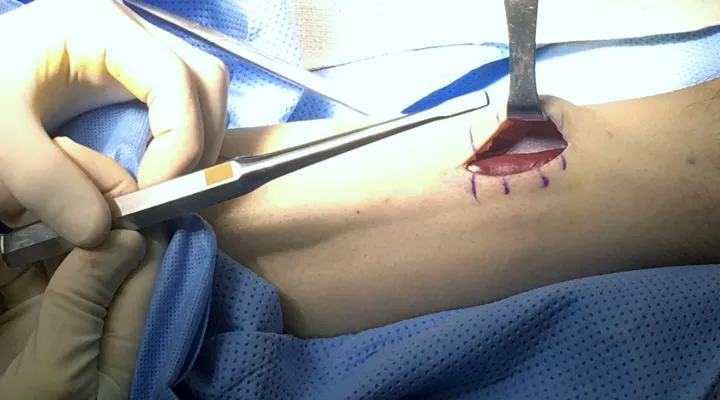

Intra-operative image of open fasciiotomy for chronic exertional compartment muscle syndrome where the bulging muscle belly can seen at the center of the image from build up of pressure within the compartment.

The following is the fascial covering over a muscle compartment. The condition occurs when pressure within this compartment builds up after an injury or can also occur after excercise from the inability of the muscle to decompress naturally. This leads to pain that is unrelenting and could lead to decreas blood flow and oxygen to muscle tissue causing death of that tissue.

The picture below demonstrates the fascia overlying the tissue being lifted by the forceps at the top of the picture.

Below is demonstrates incision into the compartment exposing the muscle tissue that is a deeper red color where the retractor is to the left of the picture. The opening of the this fascial tissue is vital in releasing pressure in the compartment after injury or from excercise. It also important that this release be extensive as so the fascial tissue does not heal closed allowing build of pressure again.